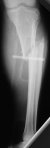

Молодой женщине по поводу бамперного перелома через 2 недели после травмы выполнен остеосинтез большеберцовой кости гвоздем ChM в одной из больниц Москвы. Снимок приложен. Сейчас речь пошла об удалении гвоздя и остеосинтезе пластиной. Действительно ли это оптимальный план? Какие есть еще варианты?

A female 24 years old, a sister of a friend of mine (not physician) living in Moscow, 3 weeks ago admitted to the hospital in Moscow after a car accident (was a pedestrian) with a tibial shaft fracture. 3 days ago closed locked nailing was performed, see attached films. Now he is in panic because they are going to remove the nail and perform plating.

The tibia shaft fracture (proximal 1/3 of the shaft) is apex medial 20 degrees, slightly short and a few degrees apex anterior after nailing. The nail extends quite proximal to the entry site. I wasn't able to see the distal end of the nail on my screen and am not certain if there was distal locking.